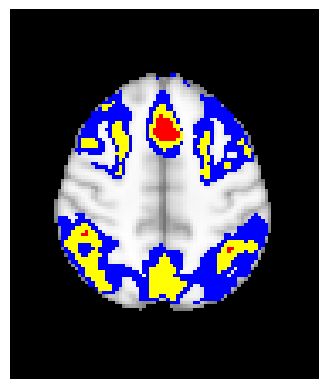

The confidence regions are constructed on fMRI scans from 77 subjects as a real data application of the proposed methods after applying additional smoothing with Gaussian kernel with FWHM to match the results shown in Bowring (2019) [BOWRING2019116187]. Confidence regions using 1) the joint method with , 2) the separate method with BH adjustment for upper and lower side each with , 3) the separate method with BH adjustment for upper side and two-stage adaptive procedure for lower with , and 4) SSS () were compared with threshold level 1.0%, 1.5%, and 2.0% Blood Oxygenation Level Dependent (BOLD) change. Joint control confidence regions are produced with instead of 0.05 for the reasons mentioned in chapter 3.

For all slices, FDR controlling methods show tighter inference of both upper and lower CR compared to the SSS method. SSS shows smaller upper CR and larger lower CR which suggests more conservative inference compared to FDR controlling testing based methodologies. This is due to the fact that by controlling for FDR, the method allows for more false discoveries in exchange for more discoveries in general. Despite having higher level at , joint control confidence regions still show comparable results to other methods even with higher significance level. Naturally, as the threshold goes up, the area enclosed between the upper and lower confidence regions decreases.

Confidence regions with separate controls of FDR for lower and upper are presented in two forms for comparison: one with BH procedure for the lower confidence region, and the other one with the two-stage adaptive procedure for the lower confidence region. The upper confidence region remains the same as both methods uses BH procedure for the upper set FDR control. Lower confidence regions with adaptive method are smaller than lower sets with BH procedure which is to be expected as the two-stage adaptive procedure is less conservative when more voxels are thought to be rejected. In the context of negative one-sided testing, this is equivalent to when there are less number of voxels above than below .